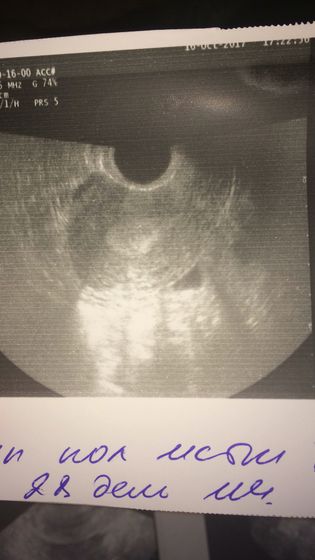

Всем привет! Пост нытья( Сегодня 29 дц из 28, сегодня должны были начаться М, но нет ни их, ни намёка. Тесты на 12 и 13 дпо отрицательные ( и Грудь болит, живот потягивает только если хочу в туалет по маленькому, вчера на УЗИ эндометрий 16мм и ЖТ в левом яичнике. На участке эндометрия есть более светлый участок, по словам врача это скорее всего полип. На УЗИ на 5 дц ничего не видели такого( в этом цикле нет обычной мазни перед месячными. Врач сказала повторить УЗИ на 5-7 дц ещё раз, чтоб исключить / подтвердить полип, но когда будет этот 5-7 дц неизвестно((( гормоны в норме в этом цикле, только прог на нижней границе — 2,6 при норме от 1,7, но все врачи говорят что норм, повышать не надо. А я не могу понять откуда за две недели взялся полип, почему нет М вовремя (и они сегодня не начнутся 100%). Девочки, у кого был такой прог — поднимали? И кто прошёл через гистеру- как быстро разрешили планировать и когда все получилось?